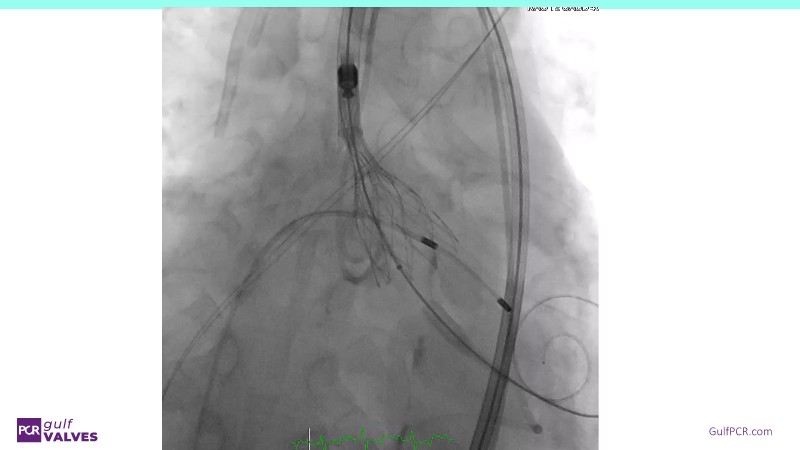

Discover a selection of cases showcasing the key features of the Navitor Valve System and its clinical applications. This session explores auxiliary access, the use of Navitor in alternative access and complex PCI, its performance in challenging peripheral anatomies, and innovative outcomes with the Vantage 30D system.